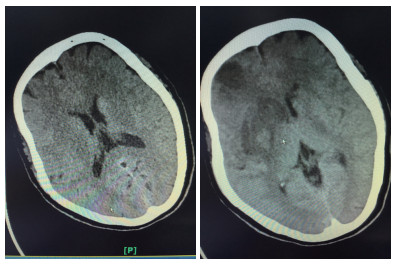

溶栓后第1天复查头颅CT

患者女性,55岁,住院号:526777。主诉:左侧肢体乏力1 h余。现病史:缘于入院前1 h余始无明显诱因出现左侧肢体乏力,持物、行走不能,伴有构音含糊,无吞咽困难、饮水呛咳,无意识障碍,无抽搐、二便失禁,无头晕头痛呕吐,无畏冷发热,无咳嗽咳痰,无心悸气喘,无腹痛腹泻,无双下肢水肿。在外未诊治,急诊行头颅CT后送入本科。既往史:无。个人史:无烟酒嗜好。体格检查, 查体:体温: 36.5℃, 脉搏: 72次/min, 呼吸: 20次/min, 血压: 126/76 mmHg。双肺呼吸音清,未闻及干湿性啰音;心率72次/min,律齐,各瓣膜区未闻及杂音;周围血管征阴性;专科查体:神志清楚,构音含糊,对答切题,双眼向右侧凝视,左侧鼻唇沟浅,口角歪向右侧,伸舌偏左,左侧肢体肌力1级,右侧肢体肌力5级,肌张力正常,深、浅感觉正常,膝反射、跟腱反射等腱反射对称活跃,克匿格征、布鲁金斯基征阴性,左侧巴彬斯基征阳性,右侧病理征未引出,共济运动及闭目难立征欠合作。NIHSS评分14分。辅助检查:头颅CT示双侧基底节区腔隙性脑梗死;入院诊断:①脑梗死②糖尿病?治疗;患者处于溶栓时间窗,入院后完善相关检查无明显溶栓禁忌证,经家属同意,予阿替普酶溶栓(患者体质量55 kg,予阿替普酶50 mg溶栓,其中5 mg静推,余剂量予1 h泵入),并予“吡拉西坦8 g静滴,1次/d,依达拉奉30 mg静滴,2次/d”等治疗,第2天患者左侧肢体乏力、构音含糊较前改善,查体:构音稍含糊,双眼无凝视,左上肢肌力1+级,左下肢肌力3级,溶栓后第1天复查颅脑CT平扫:右侧基底节区及额颞叶大面积脑梗死,并右侧基底节区出血性脑梗死可能性大(阅片考虑可疑高密度灶非出血灶,考虑正常脑组织),予加用波立维75 mg,1次/d、立普妥20 mg每晚睡前1次、尤瑞克林0.15 PNA静滴,1次/d。溶栓后第2天颅脑MR平扫(1.5T):①双侧基底节区、双额叶多发梗死灶、腔隙灶。②脑干腔隙灶?③部分空泡蝶鞍。患者住院共11 d,出院时患者左侧肢体乏力、构音含糊较前改善,查体:构音稍含糊,双眼球活动正常,左侧鼻唇沟略浅,口角略歪向右侧,伸舌略偏左,左上肢肌力2+级,左下肢肌力4+级,NIHSS评分5分。